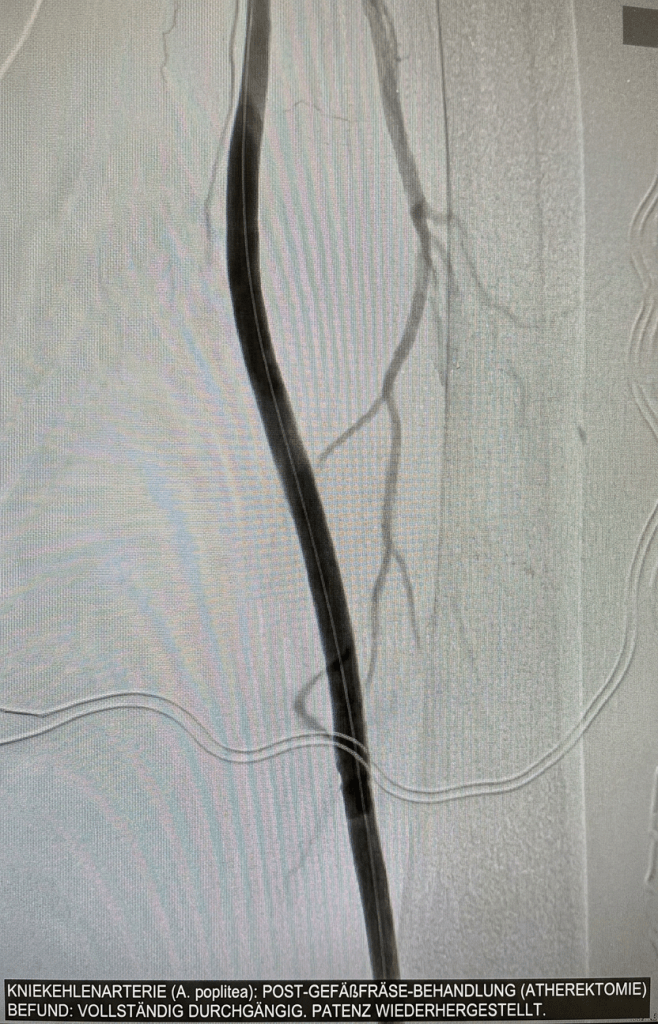

Der gleiche Patient, nachdem die Schlagader mit einer Gefäßfräse wieder eröffnet wurde